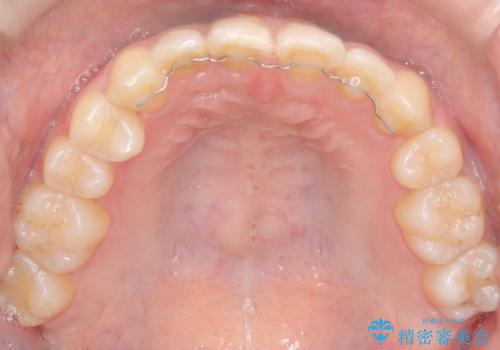

- 患者様は左上の八重歯を気にされて来院されました。八重歯による歯列の乱れだけでなく、翼状捻転(歯がねじれるように生えている状態)も見られました。目立たない矯正を希望されていたため、**インビザライン(マウスピース矯正)**を選択し、左上の小臼歯を抜歯してスペースを作りながら歯を並べる治療計画を立てました。しかし、治療の途中で翼状捻転の改善が十分に進まなかったため、患者様の希望も踏まえ、上顎のみワイヤー矯正に変更することとなりました。

治療開始時はインビザラインを使用し、全体の歯並びを整えながら抜歯スペースを活用して歯を後方へ移動させました。しかし、左上の八重歯のねじれが強く、マウスピースのみでは十分にコントロールできないことが判明。そこで、より細かく歯を動かすために上顎のみワイヤー矯正へ切り替えました。ワイヤー矯正によって翼状捻転も改善し、最終的にバランスの取れた歯並びと噛み合わせを実現。患者様からは「長い治療だったけれど、しっかり整って満足」と嬉しいお言葉をいただきました。